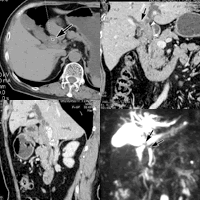

病历摘要 患者女,67岁,出现黄疸1个月余,伴皮肤搔痒,粪便呈灰白色1周,无腹痛。影像学检查如下图所示,诊断为胆总管癌。手术的病理结果为低分化腺癌。

图1 CT平扫,胆总管增粗,呈均匀软组织密度,CT值43HU(箭号)

图2,图3 CT延胆总管长轴曲面多平面重组影像(MPR)冠状位(图2),矢状位(图3),示肿瘤沿胆总管生长(箭头),并侵犯肝管与肝右叶肝管(箭号),伴肝内胆管扩张

图4 MRI水成像,可见胆总管上段至肝总管信号缺损,代表肿瘤部位(箭号),伴肝内胆管扩张, http://www.100md.com